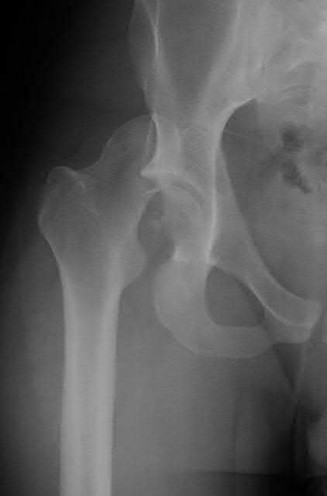

Question 1

A 12-year-old obese boy presents with vague left thigh and knee pain. He is diagnosed with a Slipped Capital Femoral Epiphysis (SCFE) as seen in similar clinical scenarios.

During percutaneous in-situ fixation, unrecognized penetration of the guide wire into the hip joint occurs. What is the most likely specific complication resulting from this technical error?

Explanation

Chondrolysis is a severe complication of SCFE characterized by rapid destruction of the articular cartilage. While it can occur idiopathically, its most established iatrogenic cause is unrecognized intra-articular hardware penetration. The 'approach-withdraw' fluoroscopic technique is required during pinning to assure pins are entirely intraosseous. Avascular necrosis (AVN) is usually due to damage to the epiphyseal blood supply (retinacular vessels) secondary to the initial displacement, forceful closed reduction, or posterosuperior pin placement.